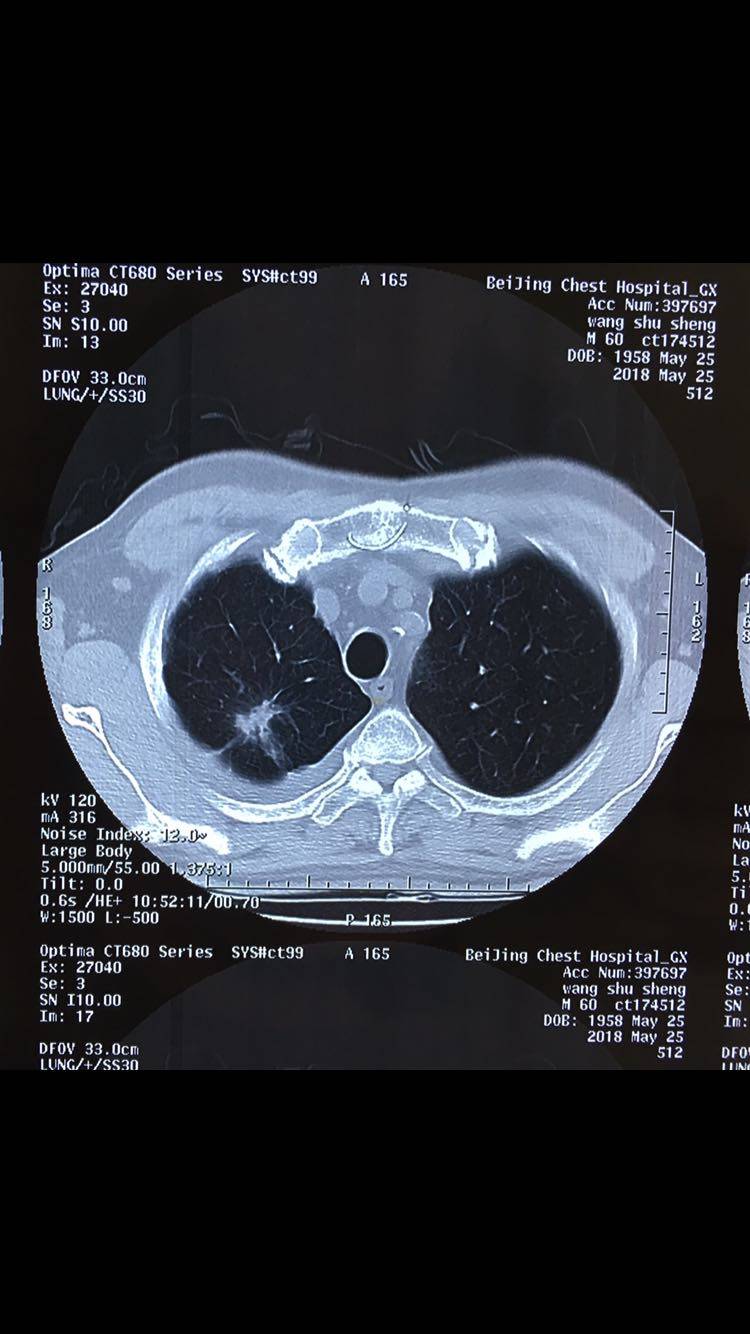

各位病友大家好,相求助听取一下大家的建议,目前患者情况很好,患者自今年三月起确诊肺腺癌晚期,目前使用贝伐珠单抗 培美曲塞 奈达铂化疗了5次,这周准备化疗第6次,主治医说想这次加上放疗同步治疗,我很犹豫,不知道如何选择。请大家给予治疗建议。患者基因检测没有靶向药。B超结果没有其他异常。这几次化疗后CT结果有病灶变小。

陈波医生放疗我也认为可以做的,但我觉得不需要同步放化疗,副作用大。化疗满6周期后,空窗一段放疗,用精准放疗去打击上肺的病灶

@陈波医生 您好,专家咨询不知道怎么回复,所以在这里给您留言不知道您是否能看到,患者的胸膜丘壮凸起和积液之前就有过,自三月开始到现在都一直控制的很好。

陈波医生好的,那比预想的要好很多。残留的胸水还能引流掉吗?如果能引流掉最好。